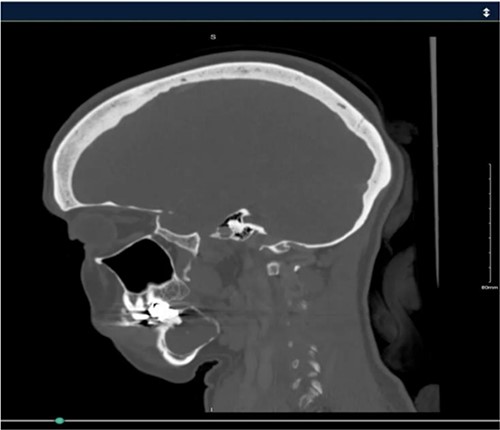

A 40-year-old woman presented with swelling on the right side of her mandible. She had completed orthodontic treatment 2 years earlier. A panoramic radiograph showed a unilocular radiolucency extending from the mandibular angle to the right first molar region (Figs 1–3).

Radiographic evidence showed expansile lytic lesions with sclerotic borders, consistent with IOS presentations [16]. Histology revealed Antoni A and B patterns, hyalinized Verocay bodies, and S-100 protein-positive cells, corroborating previous findings [17, 18].

Surgical management typically involves enucleation through a mucoperiosteal flap and a bone window, emphasizing thorough postoperative monitoring due to the risk of recurrence [19]. Imaging modalities such as CT and MRI are valuable but not mandatory [5, 19]. Our submandibular approach was effective and consistent with other studies [19, 20].